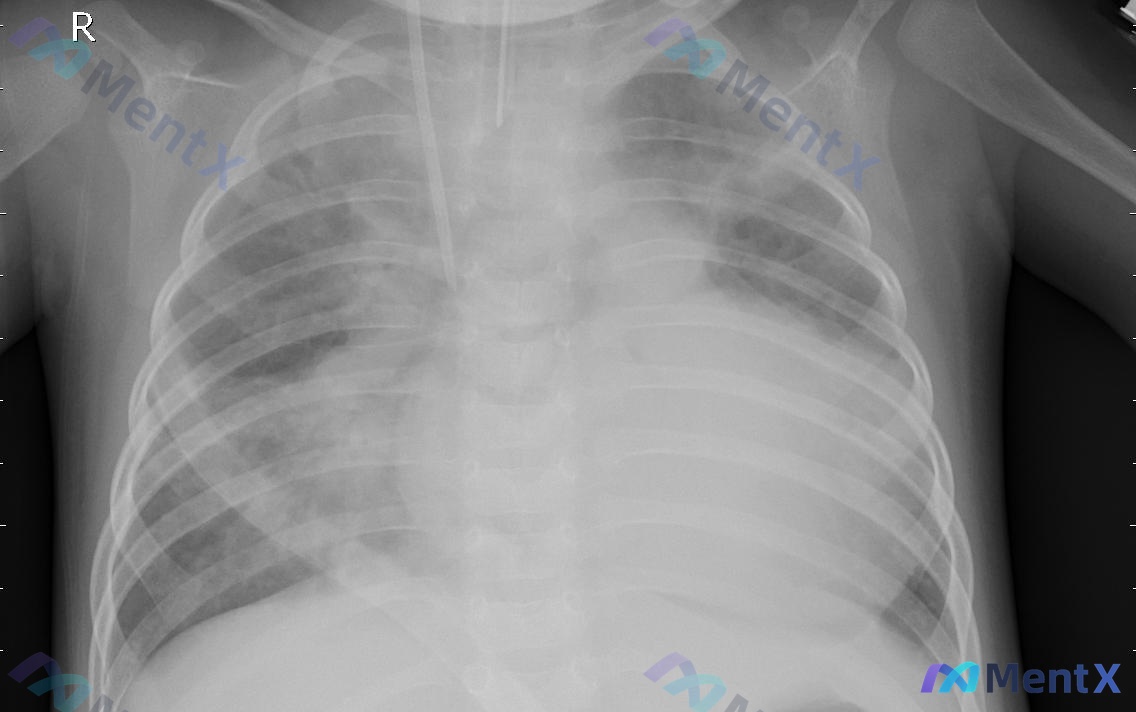

仰卧位胸片见双肺弥漫渗出,是感染还是非感染?第一眼容易踩坑

整理到一份胸部X光片的资料,先放核心信息,大家一起看看思路: 核心影像表现 - 投照体位:仰卧位(AP位)胸片 - 关键发现: 1. 双肺纹理增粗增多,双下肺及肺门周围明显; 2. 双肺散在斑片状、云絮状密度增高影,边缘模糊,以中下肺野为主; 3. 图像中央可见一根管状结构沿气管走行进入胸腔(提示内...